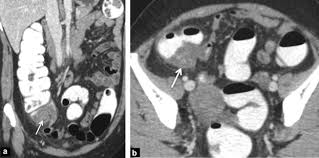

Can Colon Cancer Be Mistaken For Diverticulitis / Difference In Clinical Features Between Right And Left Sided Acute Colonic Diverticulitis Scientific Reports : Diverticulitis involves common digestive tract growths called diverticula.. (diverticulitis, appendicitis, colon cancer, chronic inflammatory disease of the intestine) should be sought for any. If left untreated, diverticulitis can lead to a collection of pus outside the colon wall or a generalized infection in the lining of the abdominal cavity, a condition known as peritonitis. The diagnosis of cancer was made within 6 months from the date. Colon cancer however is caused by small lumps that progress into cancerous tumors. Because the symptoms of ibs, colon cancer, and some other gastrointestinal.

Colon cancer can become secondarily infected and simulate sigmoid diverticulitis,. But when they do show up, the symptoms can mimic those of crohn's disease. It does not appear that diverticulitis and cancer are heavily linked, as the former is a very common condition that is generally easily treated. Went for a ct before a surgery could be scheduled for scar tissue in my abdomen. Colon cancer however is caused by small lumps that progress into cancerous tumors.

In the retrospective part of the study, 27 patients were diagnosed with diverticulitis and 31 were diagnosed with colon cancer. It does not appear that diverticulitis and cancer are heavily linked, as the former is a very common condition that is generally easily treated. Patients who present with acute diverticulitis may have significant abdominal pain and fever, which may be confused with inflammatory bowel disease or peptic ulcer disease. Diverticular disease and the risk of colon cancer. I thought i may have ovarian cancer from all the symptoms, which are painful left abdominal pain, lower backache which is constant, pain in groin and down left leg, fever and then chills, very fatigued to the point of dragging myself through the day, constipation, frequent and urgent need to urinate and now nauseus as well. When colonic obstruction is present, colon cancer is more likely than diverticulitis. Colon polyps are growths on the inner lining of the colon, and diverticulitis happens when a diverticulum ruptures and becomes infected. The most frequent issues with the bowel or colon, affect the colon's ability to work properly. However, people with diverticulitis may be at higher risk of developing colon polyps. Colon polyps do not cause diverticulitis. Screening for colon cancer can detect and remove precancerous polyps before they have the chance to develop into cancer. I had 10 or 12 inches of colon removed. Went for a ct before a surgery could be scheduled for scar tissue in my abdomen.

Does anybody know if they can tell the difference between diverticulitis and colon cancer on a ct scan? During diverticulitis, diverticula become infected or inflamed. Although at first diverticulitis and colon cancer may present similar symptoms, they are two very different conditions. Primary colonic gi lymphomas (usually diffuse large b cell), however, can be mistaken for ibd on colonoscopy. Most times it occurs when small pouches called diverticula become infected or swollen.

Diverticulitis is a condition set off by infection or rupture of diverticula,. Sure, a ct scan can be consistent with diverticulitis, but many other conditions can precisely mimic this ct scan appearance. I was diagnosed with diverticulitis with a severe infection; It does not appear that diverticulitis and cancer are heavily linked, as the former is a very common condition that is generally easily treated. Symptoms of diverticulitis and colon cancer may include abdominal pain. The most frequent issues with the bowel or colon, affect the colon's ability to work properly. August 8, 2009 at 12:09 pm. Yes diverticulosis is benign, has distinct appearance from ca on ct for a trained radiologist will read as accurate as reading finger prints, some times in between diverticula the wall may be thickened, may have mucosal overgrowth will mimic a early cancer, then colonoscopy indicated, at 39 cancer is not common but age is not exception for ca, ask again for referral. Diverticulitis involves common digestive tract growths called diverticula. Screening for colon cancer can detect and remove precancerous polyps before they have the chance to develop into cancer. Patients who present with acute diverticulitis may have significant abdominal pain and fever, which may be confused with inflammatory bowel disease or peptic ulcer disease. When colonic obstruction is present, colon cancer is more likely than diverticulitis. Although at first diverticulitis and colon cancer may present similar symptoms, they are two very different conditions.

(diverticulitis, appendicitis, colon cancer, chronic inflammatory disease of the intestine) should be sought for any. It was just suppose to be a routine ct scan before a surgery. The findings most specific for diverticulitis were pericolonic. I thought i may have ovarian cancer from all the symptoms, which are painful left abdominal pain, lower backache which is constant, pain in groin and down left leg, fever and then chills, very fatigued to the point of dragging myself through the day, constipation, frequent and urgent need to urinate and now nauseus as well. Considering the ambiguity of these symptoms, it's not surprising that colon cancer is often misdiagnosed as a benign case of diverticulitis.